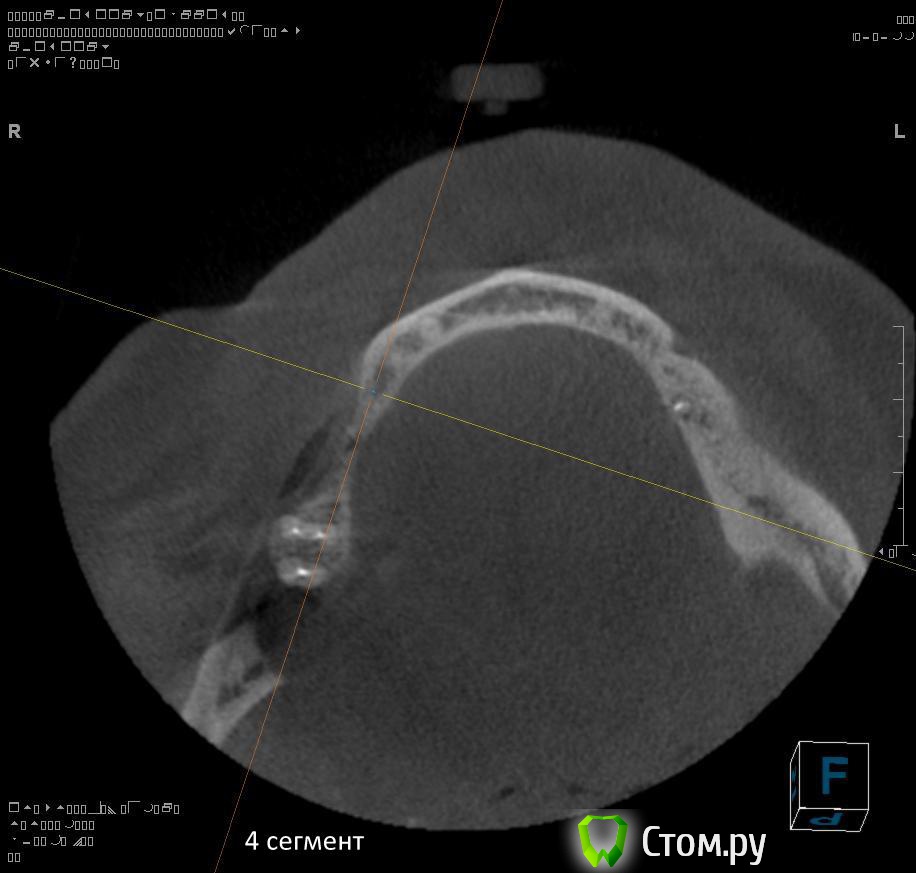

4. через 1,5 - 2 месяца после удаления 4.4 и 4.7 провести установку имплантатов в 4 сегменте?

5. в какие позиции должны быть поставлены имплантаты в 4 сегменте сбоку (4.5, 4.7?)?

Там подойдет любая каркасная техника. Расщеплять бы не стал, если отломиться и резорбируется будет совсем печально.